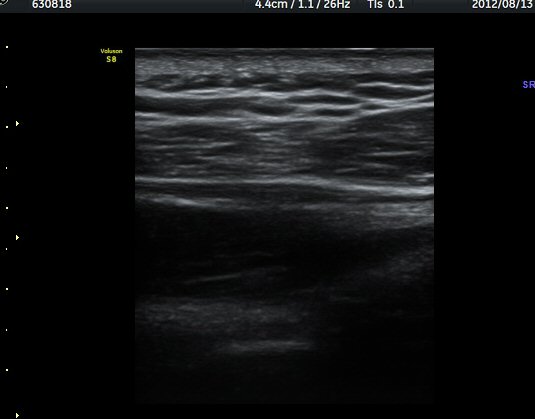

ÁÖ»ç¹Ù´Ã ÈíÀÎ(µ¿¿µ»ó Âü°í) 4ÀÏ ÈÄ °üÂûÇÑ ¼Ò°ß¿¡¼­´Â ³¶Á¾ÀÇ Å©±â °¨¼Ò°¡ ¶Ñ·ÈÇÏÁö ¾Ê´Ù(±×¸² 5, 6).

ÈíÀÎ 14ÀÏ ÈÄ ÃÊÀ½ÆÄ°Ë»ç¿¡¼­ ¾à°£ÀÇ ³¶Á¾ Å©±â °¨¼Ò°¡ °üÂûµÈ´Ù(±×¸² 7, 8)